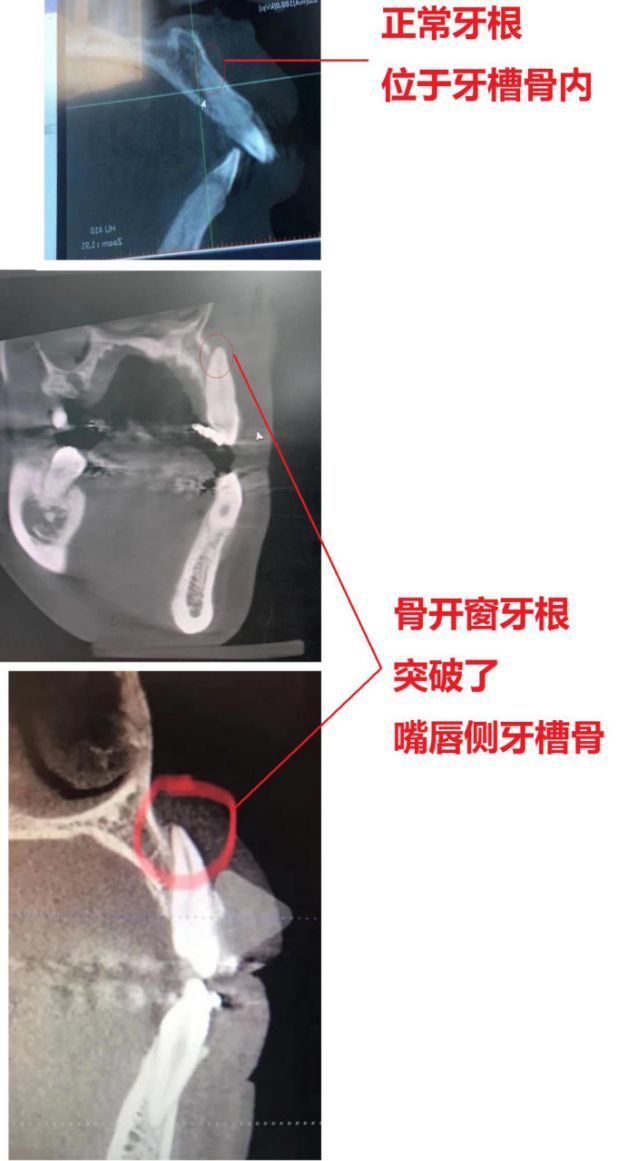

《正畸案例41:正畸中的骨开裂与骨开窗》

《正畸案例41:正畸中的骨开裂与骨开窗》